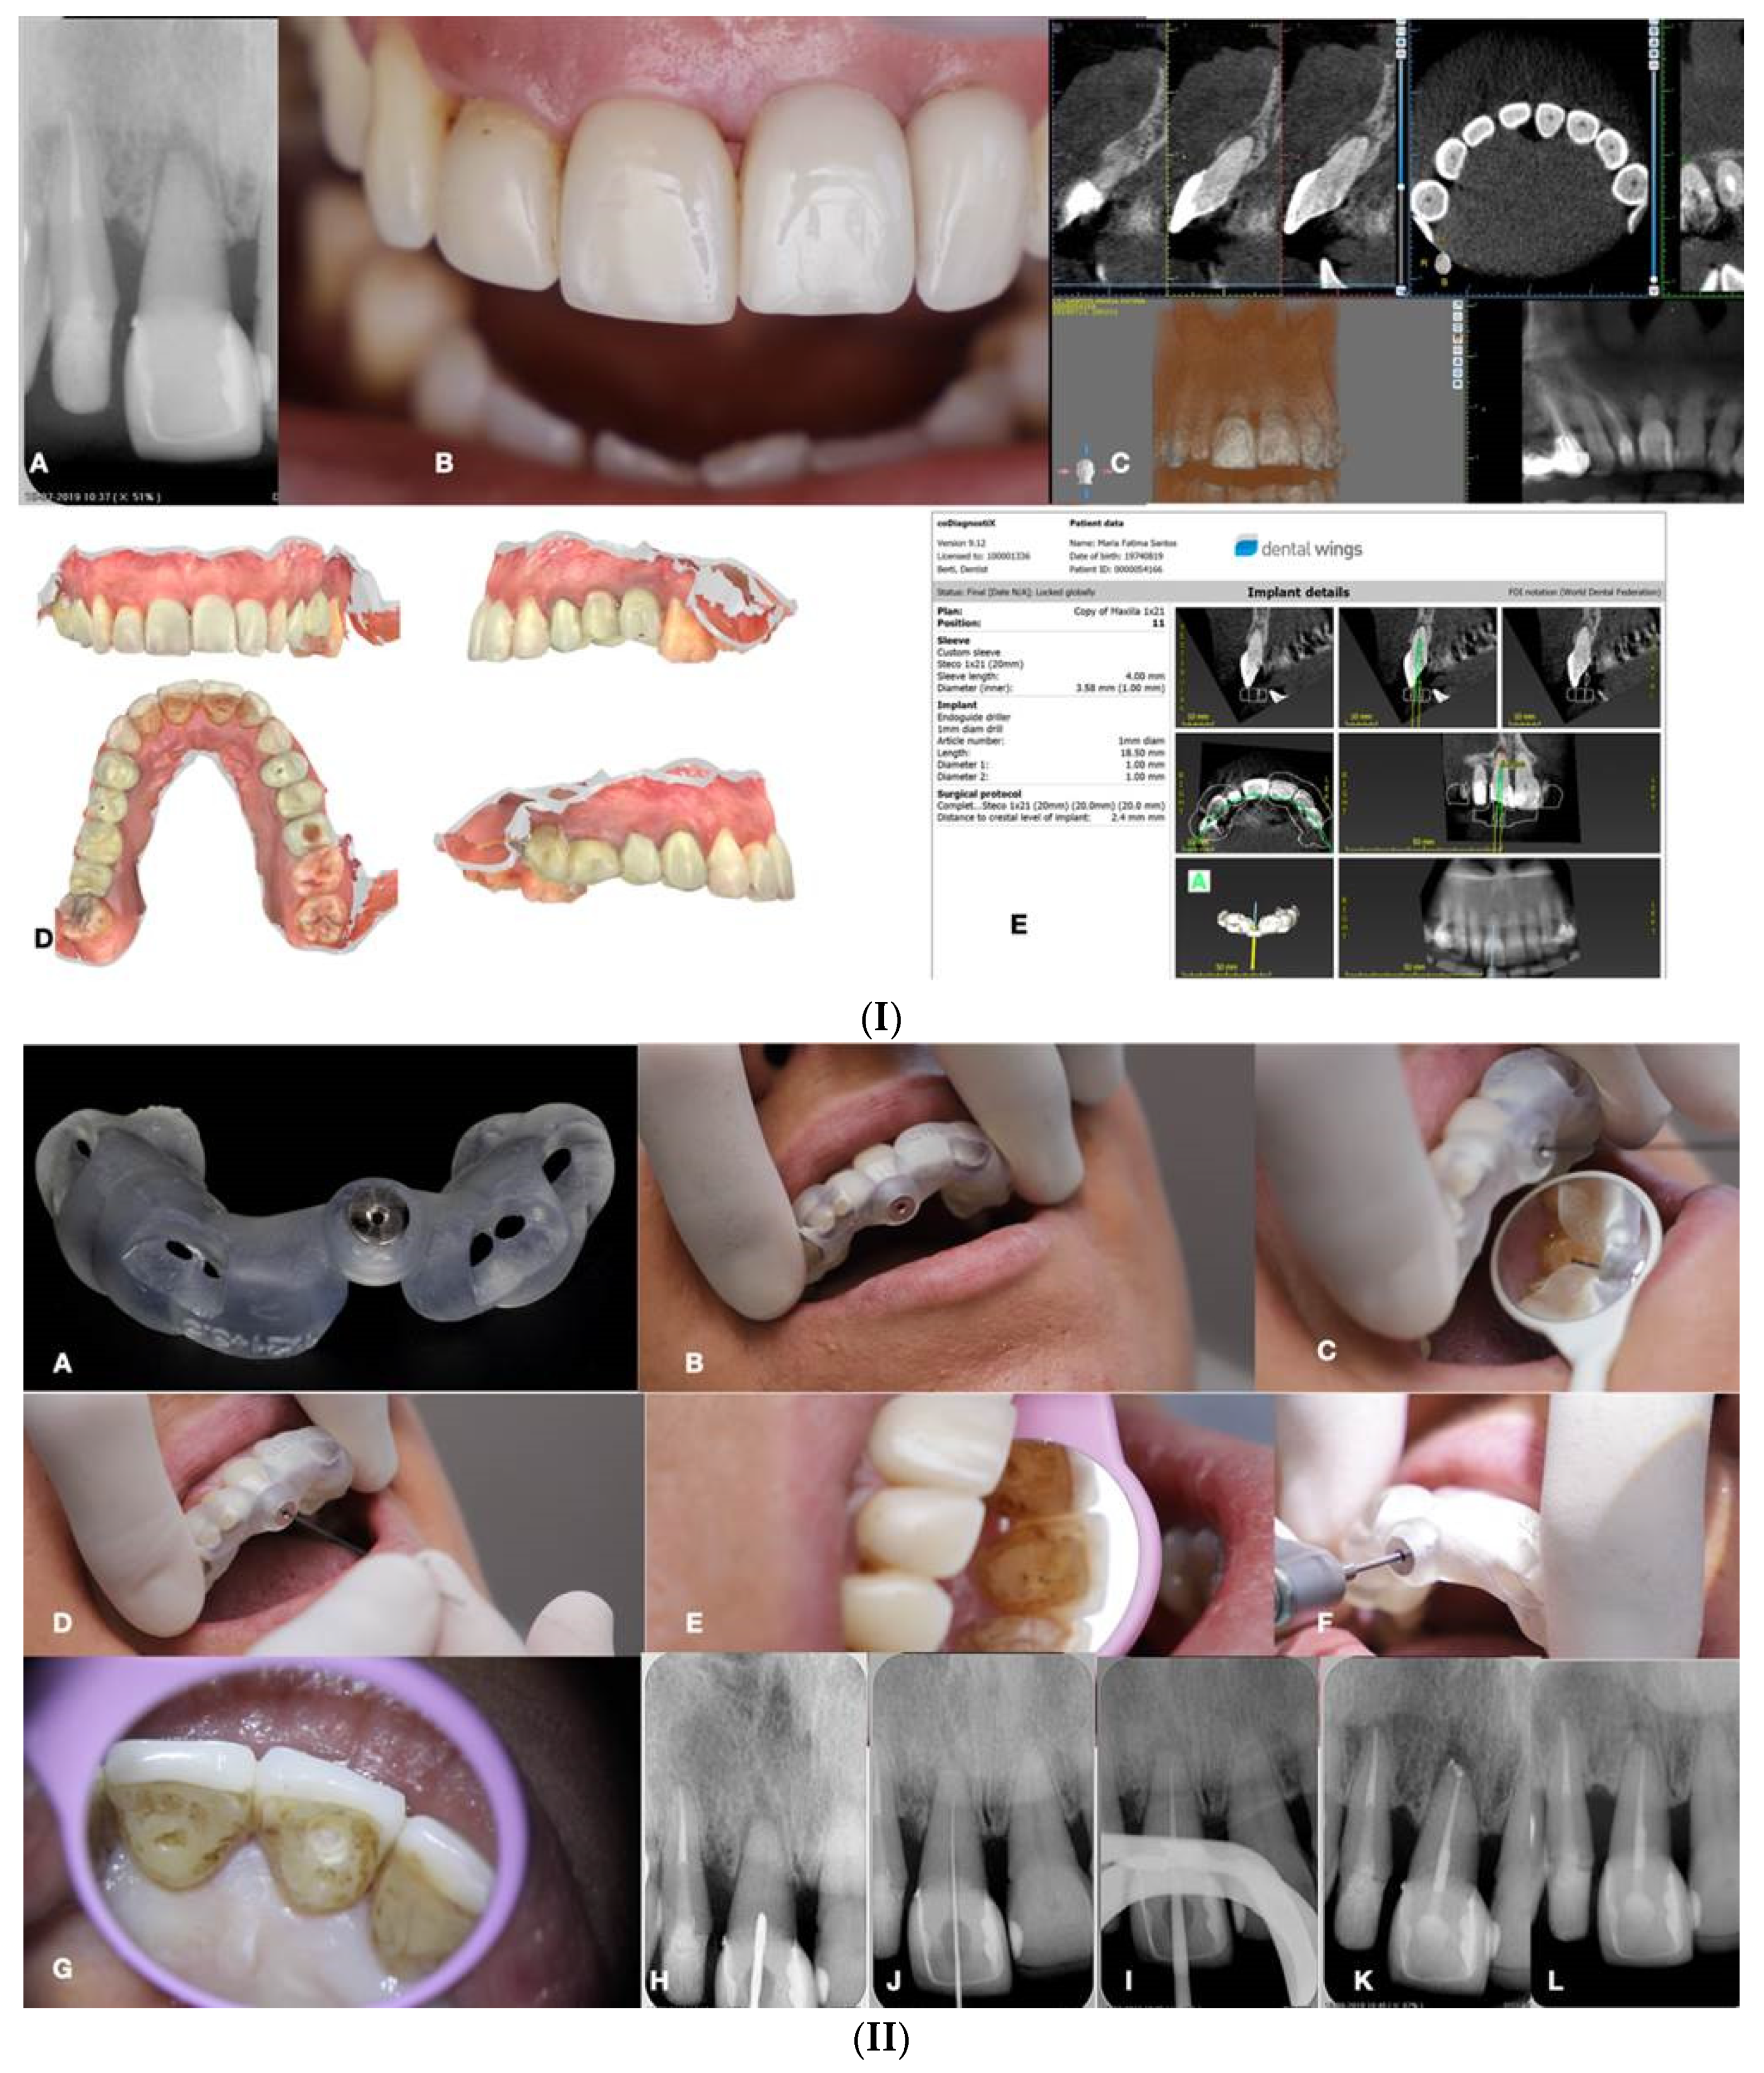

10. Static Guided Technique

This technique combines the use of a guiding template in conjunction with CBCT, which facilitates the location of severely calcified root canals (

Figure 15) (de Toubes et al. 2017, Connert et al. 2018, Fonseca et al. 2018, Lara-Mendes et al. 2018, Shi et al. 2018). The guide design is based on the anatomy of the root canal and the architecture of the tooth and adjacent structures, which were obtained by CBCT images and an impression or intra-oral surface scan, respectively (

Figure 15) (Nayak et al. 2018).

Special software like coDiagnostiX (Dental Wings Inc, Montreal, Canada), associated with CBCT data and 3D intra-oral scan were superimposed to allow virtual planning of the access cavity (Nayak et al. 2018, Fonseca Tavares et al. 2018). After this, a 3D virtual template was produced to obtain the physical model of the endodontic guide that will orientate the burr into the calcified root canal (Nayak et al. 2018, Fonseca Tavares et al. 2018). Static-guided access through PCO cases in anterior teeth has been previously reported in the literature and described as a safe and predictable technique to give minimal invasive access to calcified canals. This may help to preserve tooth structure avoid technical errors, and lead to an improvement in the long-term prognosis (Lara-Mendes et al. 2018a, 2018b).

Krastl et al. (2016) were the first to describe a static guided technique in vivo, on maxillary central incisor with PCO and apical periodontitis. This technology was first described in implantology and after applied to endodontics, surgery, and conventional access (Buchanan 2018).

The present method consists of accessing and locating root canals through a guiding template created by tomographic planning (Lara-Mendes et al. 2018a, 2018b). The guiding template sleeves direct the position of the access burrs, increasing the perforation precision during the access and reproducing adequate tomographic planning (

Figure 15).

Access guides are manufactured by overlapping the CBCT data with an intraoral scan of the target area (Malhorta et al. 2013, Lara-Mendes 2018).

The CBCT is essential for the preoperative visualization of the exact location and anatomy of the root canal system in complex cases (Malhorta et al. 2013). Although CBCT is associated with higher radiation doses, it has contributed to increasing the success rate of endodontic treatments by optimizing technical preoperative treatment planning (Lara-Mendes et al. 2018). In 2015, the American Association of Endodontists and the American Academy of Oral and Maxillofacial Radiography updated their guidelines on the use of CBCT imaging in endodontics. They recommend CBCT imaging for the location of calcified root canals because of the high level of difficulty associated with this procedure (Lara-Mendes et al. 2018).